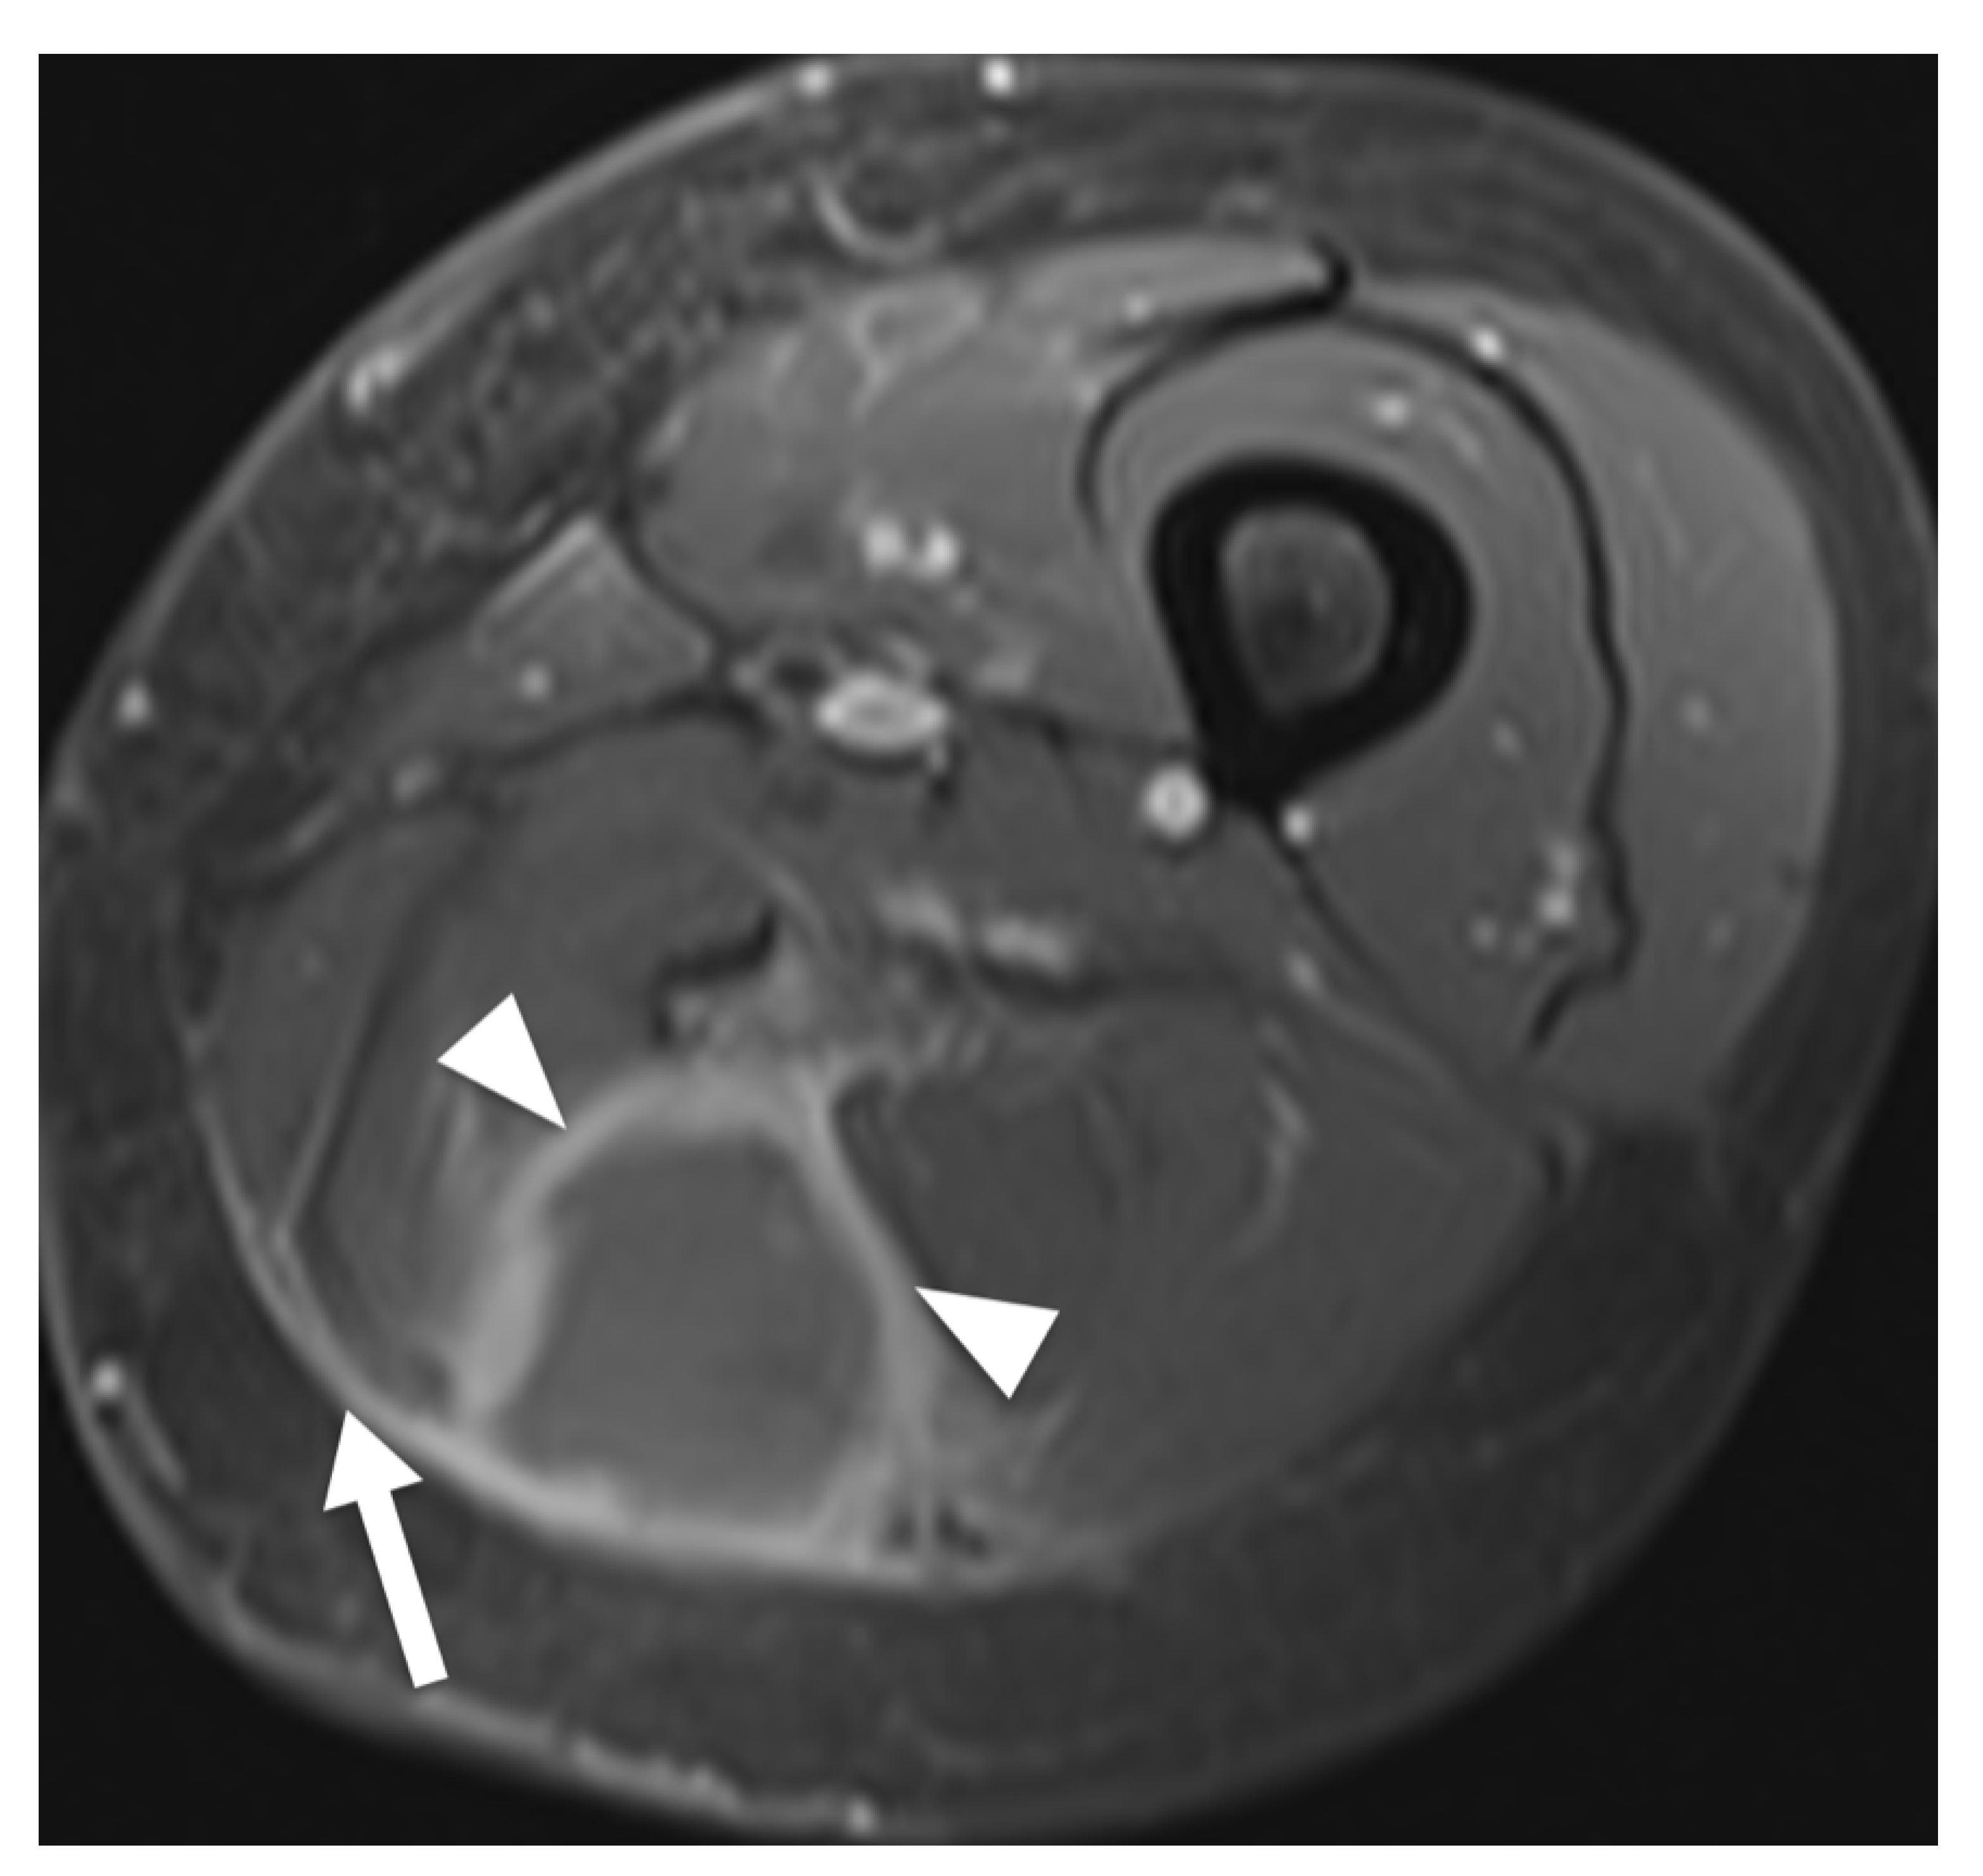

4. Discussion